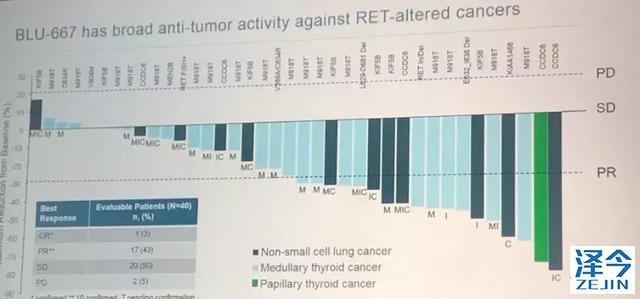

BLU-667表现出广泛的抗肿瘤活性,对于接受剂量≥60mg且具有至少1次基线后应答评估的RET改变患者,总体反应率(ORR)最高为37%(95%CI,20%-56%) (n = 30)。特别是非小细胞肺癌和MTC患者的ORR分别为50%和40%。在具有RET融合和突变的患者中,ORR为45%。

40例可评估患者中,1例完全缓解,17例部分缓解,20例病情稳定,2例进展。

Subbiah教授也是靶向治疗临床中心的副主任医师,他指出这些结果令人鼓舞,因为无论肿瘤类型如何,都可以看到广泛的抗肿瘤活性。